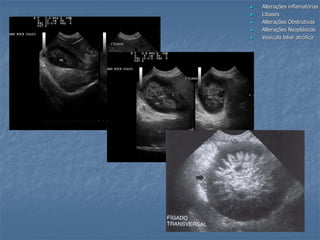

Obstrução Biliar Extra-Hepática (cães)

 Sinais de obstrução

Pesquisa da etiologia da obstrução/ compressão:

- Inflamatória (fígado, pâncreas e TGI)

- Cálculos

- Tumores (fígado, pâncreas, linfonodos, duodeno)

cálculos abscesso

DBC

gordura

pancreatite

colelitíase

colangiocarcinoma

colangite e pancreatiteInflamação pielogranulomatosa com fibrose